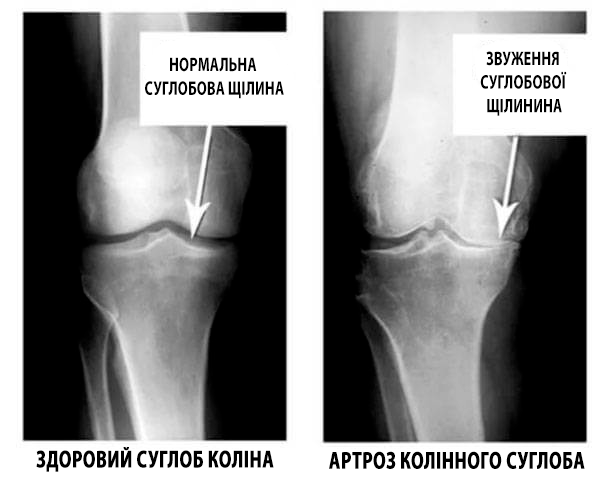

Погляньте на ці знімки, ви бачите, що на правому знімку суглобова щілина відсутня, кістки труться один об одного, викликаючи сильний біль. І цей процес дуже важко зупинити! Через пару років людина стане інвалідом і не зможе себе обслуговувати.